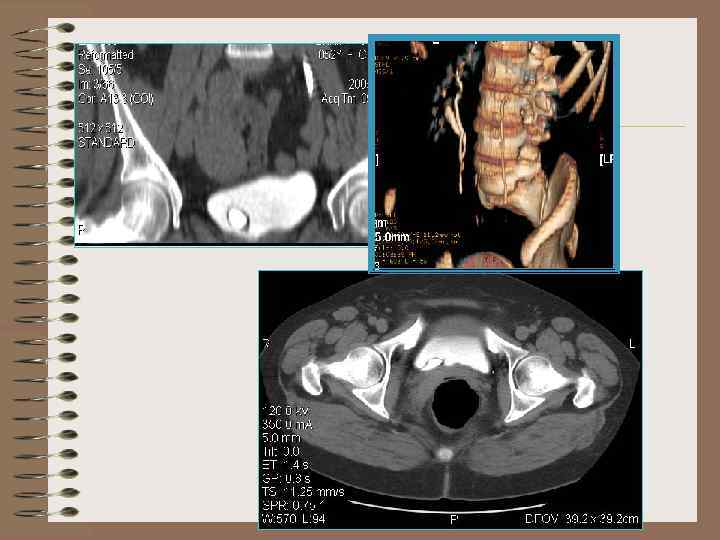

Добавочная третья почка • Крайне редкая аномалия • Две почки расположены в типичном месте • Третья почка имеет самостоятельное кровоснабжение

КТ – гипоплазия левой почки